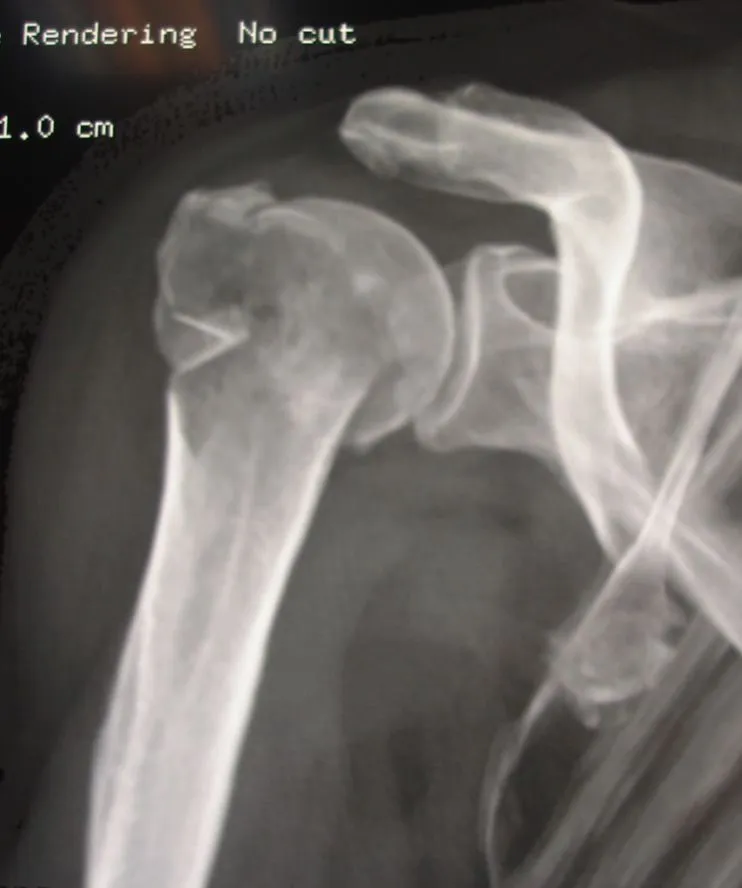

Dans un premier temps, des radiographies permettent d'avoir une orientation diagnostique en corrélation avec l'examen clinique du chirurgien. Ce bilan de débrouillage sera complété si nécessaire par un scanner.

Les fractures de l'extrémité supérieure de l'humérus représentent 6 % des fractures du corps humain. Il s'agit donc de fractures relativement fréquentes mais qui n'ont pas toutes le même pronostic.

On distingue :

- Les fractures extra-articulaires : fracture du col chirurgical de l'humérus, fractures diaphysaires

- Les fractures articulaires simples : fracture du trochiter, fracture du trochin

- Les fractures articulaires complexes : fractures céphalo-tubérositaires

- Les fractures-luxations : simples ou complexes, associant aux lésions osseuses des lésions capsulo-ligamentaires